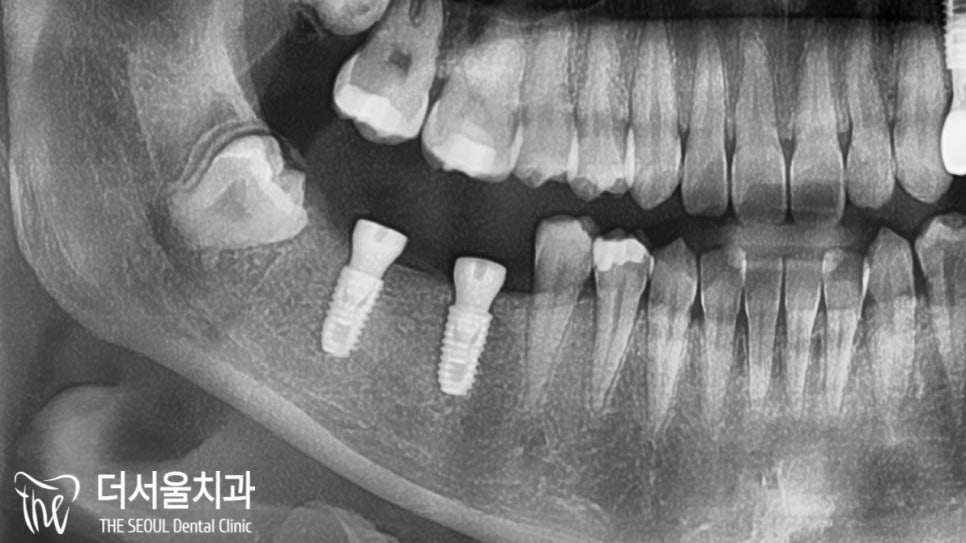

오른쪽은 보시다시피

잔존치근과 충치가 존재했습니다.

정밀 검진을 진행한 결과,

하악 46번은 잔존치근만 남아있어

이미 살리기엔 늦었다는 판단이 들었으며,

47번 충치 또한 상당 부분 진행되어

이미 신경 부근까지 감염되어 있던 상태였습니다.

오랜기간 잔존치근만 남아있었기 때문에

치조골이 소실되어 있진 않을까 걱정이 되었는데요.

다행히 별 다른 문제 없이

식립을 도와드릴 수 있을 것 같네요.

별다른 문제 없이

치조골에 단단히 심어진 모습입니다.

픽스쳐를 심고 나서

치유지대주(healing abutment)까지 체결을 도왔습니다.